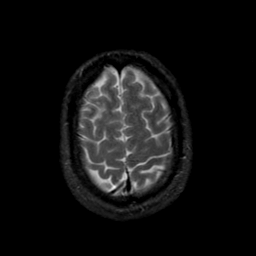

MR Study #23, January 26, 1992 -- Slice #42